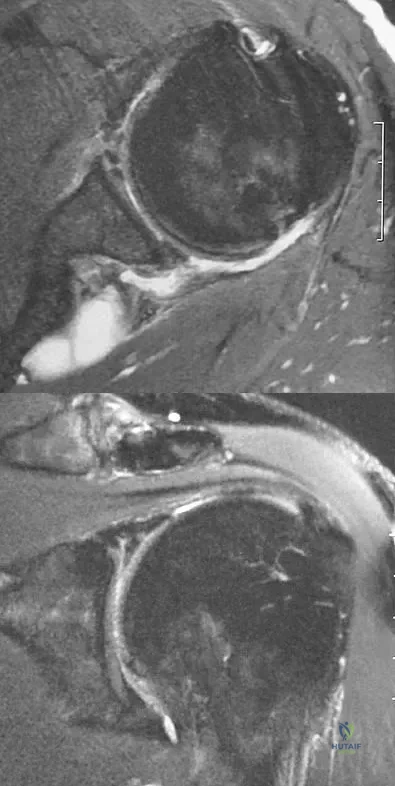

A right-handed 24-year-old professional baseball player injured his left shoulder 6 weeks ago when he dove forward and landed hard with the arm extended. He reports that the shoulder "slipped out" and "went back in." The shoulder did not need to be reduced. He now reports deep pain in the front of the shoulder when batting on either side and is hesitant to raise his left arm up over his head to catch a ball. Examination reveals no obvious deformities of the shoulder and a somewhat guarded, limited range of motion in all planes. Provocative tests for the rotator cuff and labrum are equivocal. MRI scans are shown in Figures 16a and 16b. What is the best course of action?

Explanation